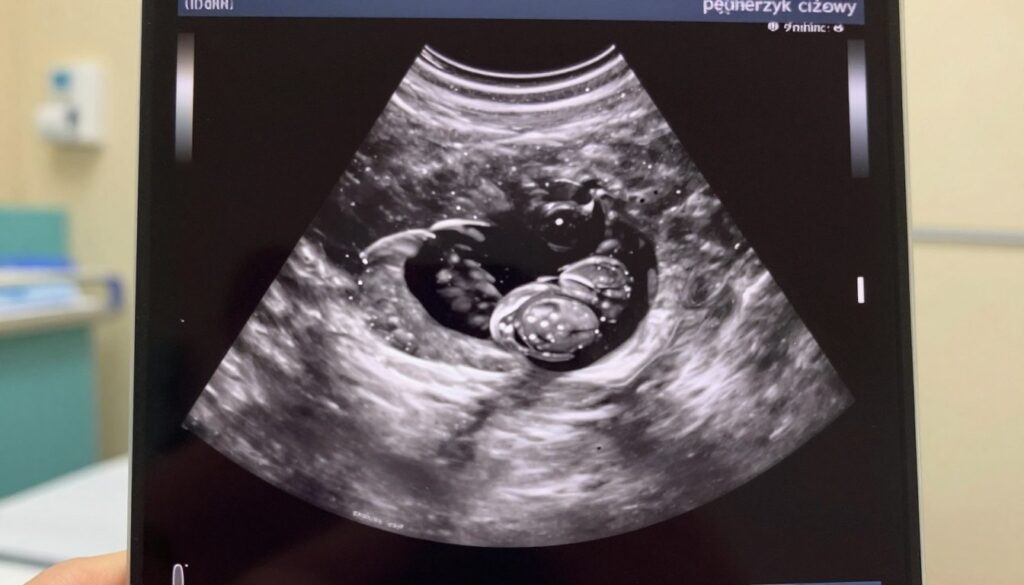

Pęcherzyk ciążowy (GS) to pierwszy widoczny element. Może pojawić się pod koniec 4. tygodnia i rośnie średnio ~1 mm na dobę.

Orientacyjne wymiary pęcherzyka: na początku 5. tygodnia ok. 3 mm, w 6. tygodniu ~10 mm, w 7. tygodniu ~18 mm.

Pęcherzyk żółtkowy (YS) zwykle pojawia się w 5.–6. tygodniu. Ma 2–3 mm na początku i może osiągać ~6 mm.

Zarodek zwykle pojawia się 1–2 dni po wykształceniu pęcherzyka żółtkowego. W badaniu dopochwowym bywa widoczny około 6. tygodnia i ma 4–6 mm.

Tętno serduszka często pojawia się zanim CRL osiągnie 6 mm, lecz nie zawsze da się je uchwycić od razu.

W praktyce ważna jest dynamika: rosnący pęcherzyk i obecność pęcherzyka żółtkowego to dobry znak, nawet jeśli echo zarodka ujawni się dopiero po kilku dniach.